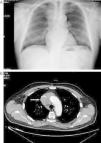

The patient is a 71-year-old male with hypertension, dyslipidemia, a history of atrial fibrillation, anti-coagulation therapy and stable ischemic heart disease. He came to our emergency department due to inflammation of the face, neck and shoulders that had been evolving over the previous 15 days without constitutional syndrome or previous respiratory symptoms. Upon physical examination, BP was 139/81mmHg, 62bpm and normal cardiopulmonary auscultation. Edema of the upper thorax, neck and face were observed. Chest radiology revealed an upper right mediastinal mass (Fig. 1). Therefore, computed tomography (CT) was ordered, which showed a mass in the upper right mediastinum that infiltrated and occluded the SVC (Fig. 1B) and small lower paratracheal and right hilar lymphadenopathies. Hemogram showed slight leukocytosis (10400/μL). Biochemistry, coagulation and tumor markers (alpha-fetoprotein, PSA, CEA, Ca. 19.9 and β2 microglobulin) were strictly normal. Abdominal–pelvic CT ruled out any alterations in other territories. Treatment was initiated with dexamethasone, which resulted in improved symptoms in the patient, and CT-guided biopsy determined the mass to be thymic carcinoma. According to the Masaoka system, it was classified as stage III–IVb (microscopic invasion of neighboring organs [SVC in this case] and lower paratracheal and right hilar lymph metastasis). The patient was discharged from the hospital with corticosteroids and continued chemotherapy treatment with carboplatin and etoposide. The patient was later administered radiotherapy in order to reduce the size of the tumor mass and achieve surgical resectability, although this was unsuccessful.